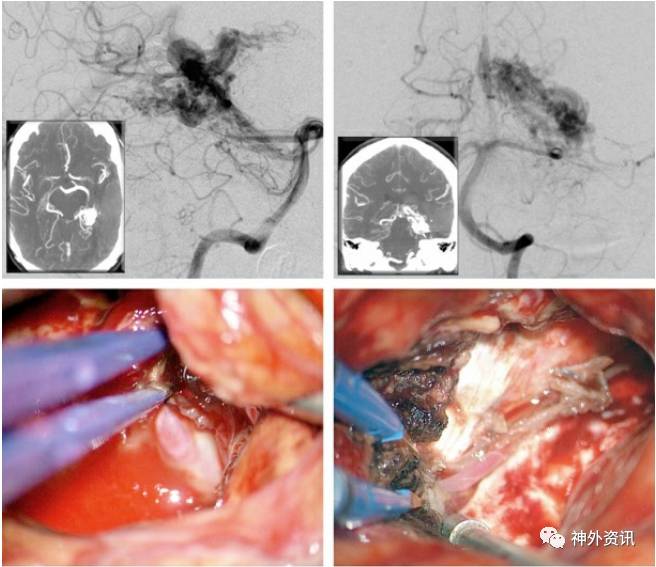

图13. 大型颞叶后内侧AVMs,主要由脉络膜前动脉供血,如图(ICA和椎动脉造影侧位像,上图)。术者采用经皮层、经脑室、经脉络裂的方法(中图)。在穿过颞角的脉络裂中显露脉络膜前动脉 (中图的插图)。AVMs完全游离后,病灶水平的脉络膜前动脉被离断,AVMs去除(下图)。所有浅静脉转为暗蓝色。

图14. 图示另一个颞叶后内侧AVMs。大多数供血动脉源自P2分支(上图)。血肿腔为经皮层入路显微外科操作提供了宽敞的空间。过度增生的P2穿支血管被切断(中图)。移除AVMs (下图)。